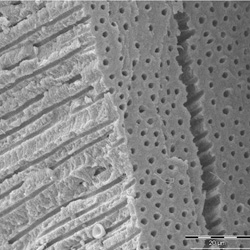

Cuando aplicamos grabado ácido total en la dentina, se retira la parte inorgánica, desmineralizándola, dejando un aspecto de red, aunque los túbulos dentinarios se siguen observando. De esta manera, quedaría sólo la materia orgánica compuesta de colágeno, pues éste no se ve afectado por el ácido ortofosfórico. Puedes observar en las siguientes imágenes las estructuras antes y luego de la aplicación del ácido.

Para esquematizar muy bien lo que ocurre con la dentina, luego de realizar el protocolo de desmineralización a través del grabado ácido, os dejamos la imagen en la que se detalla: la parte beige, sería la dentina, el amarillo más oscuro sería el túbulo dentinario y la parte en azul sería la zona que hemos desmineralizado con el ácido ortofosfórico.

Es en esta última capa (la capa híbrida), es donde vamos a tener el espacio para que se incorpore el adhesivo y genere una interface de fibras de colágeno y resina. Esta, será la que proporcione estabilidad a la adhesión. La capa híbrida es responsable tanto en esmalte como en dentina del éxito de la adhesión.

En dentina es mucho más difícil que la capa híbrida sea estable. Si la capa híbrida fuese entre 15-20 µm, se corre el riesgo de ocasionar molestias al paciente. El adhesivo al no poseer carga, podría tomar un comportamiento elástico y poseer demasiada flexión, al ser la capa muy gruesa. Si la capa híbrida mide entre 5 µm o menos, sería demasiado delgada y la adhesión fracasaría. Para una adhesión exitosa, necesitamos una capa híbrida que mida entre 8 y 10 µm.